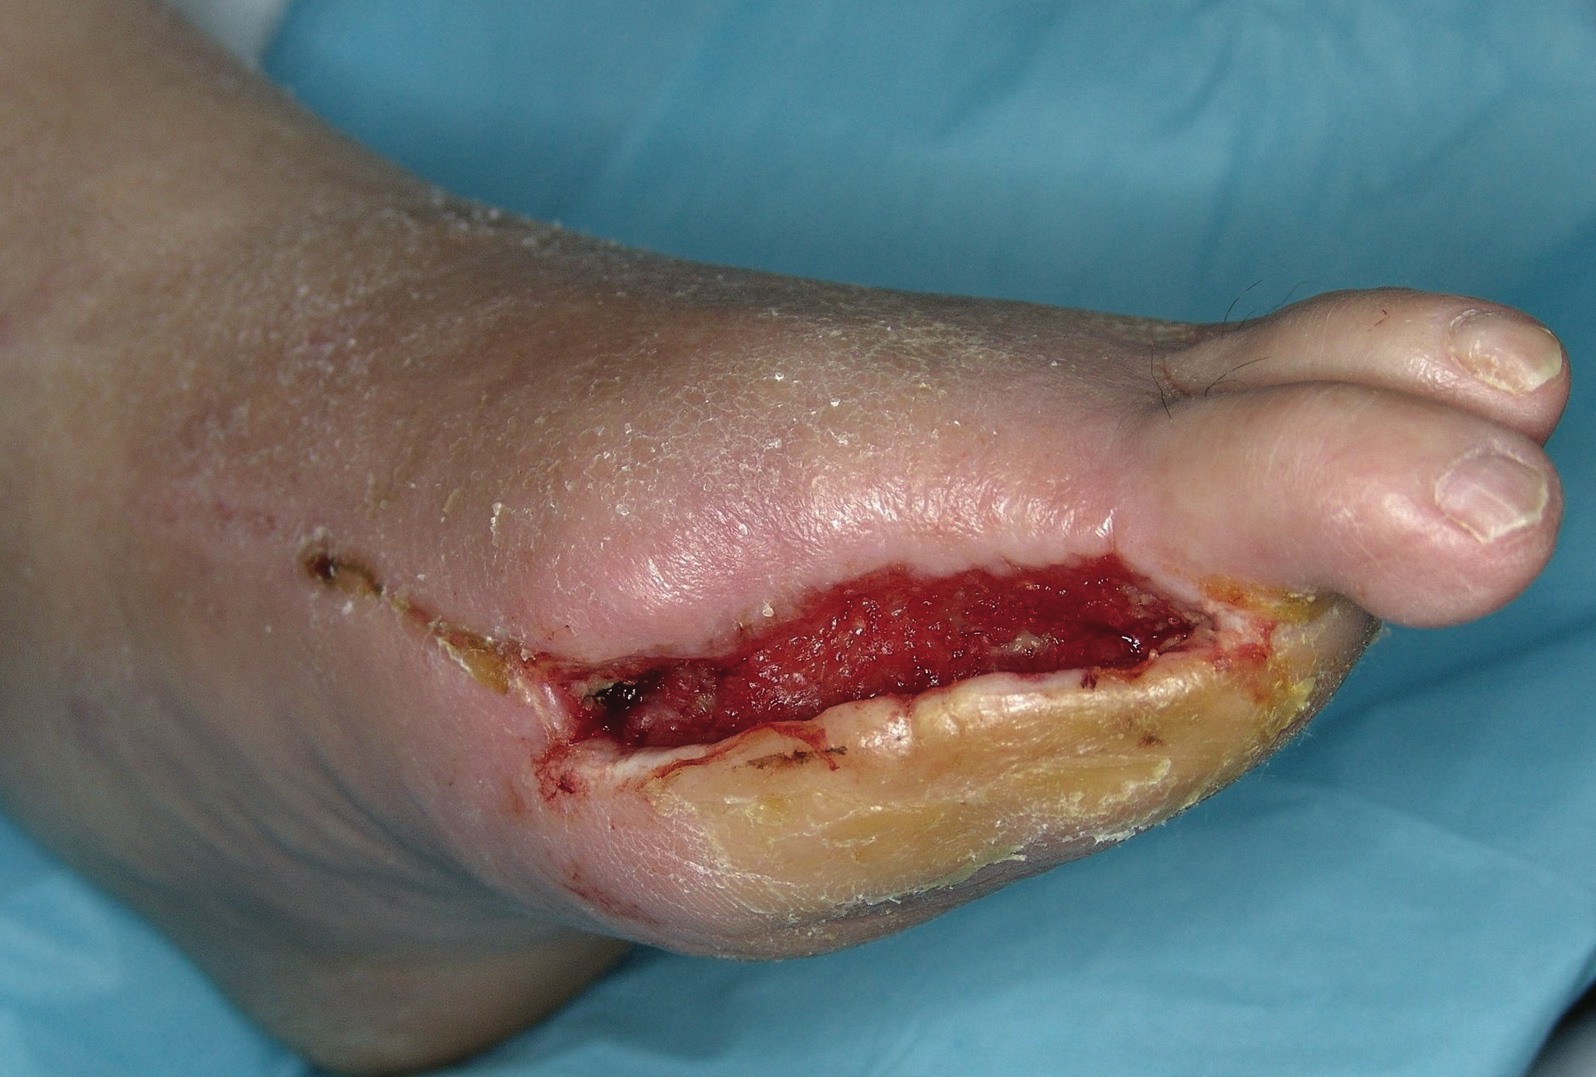

In order to use BAT products successfully, it is important to have a strong understanding of the fundamental characteristics of skin. Within the context of wound healing, there are four important components to consider. These components are the epidermis, dermis, hypodermis (subcutaneous adipose tissue) and underlying tissue. The epidermis is the most superficial component of skin. It has no direct vascular supply and sloughs continuously. The dermis is often regarded as the most important skin component to wound healing and this is where clinicians look for granulation tissue. As a key marker for healing potential, granulation tissue is literally a collection of newly formed vascular buds. As part of the standard of care, wound bed debridement involves removing nonviable tissue and inhibitory factors such as proteases and collagenases. The mechanical action of debridement disrupts the vascular buds at the surface of the wound base, causing bleeding. A bleeding wound base often indicates a viable base, which is a positive predictor for wound healing.11,12 It is also important to understand that adipose tissue and other deep tissues (fascia, tendon, bone and muscle) have the potential to form granulation tissue. Accordingly, proper debridement of these deep wound components can be essential to overall healing potential.11 The skin contains important growth factors (e.g. VEGF, PDGF) that stimulate tissue repair and angiogenesis during the process of wound healing. Bioengineered alternative tissue products generally stimulate these processes in the wound bed or can often serve to deliver growth factors extrinsically when one applies them to the wound. Some BATs contain living fibroblasts and keratinocytes in addition to growth factors. These living cell components can play an important role through the continued production of growth factors after their delivery to the wound bed. Another key role of BAT products is the matrix component, which can assist in rapid wound ingrowth and building wound integrity by providing a temporary scaffold. When selecting a particular BAT product, it is important to keep in mind the different layers of tissue and their architecture as described above. In many cases, one can choose a specific product to match the wound depth and nature. When clinicians use BAT products incorrectly, the results have a lesser degree of predicted success and the clinician may wrongly conclude that the product is ineffective or inferior. Proper selection of BAT products increases the likelihood of successful wound closure. Prior to applying these products, it is absolutely essential that the wound is clear of infection, there is adequate blood supply and there is minimal tension about the wound margins (this includes adequate offloading). When the wound bed is properly prepared for a positive wound environment, BAT products offer an effective means of promoting healing.